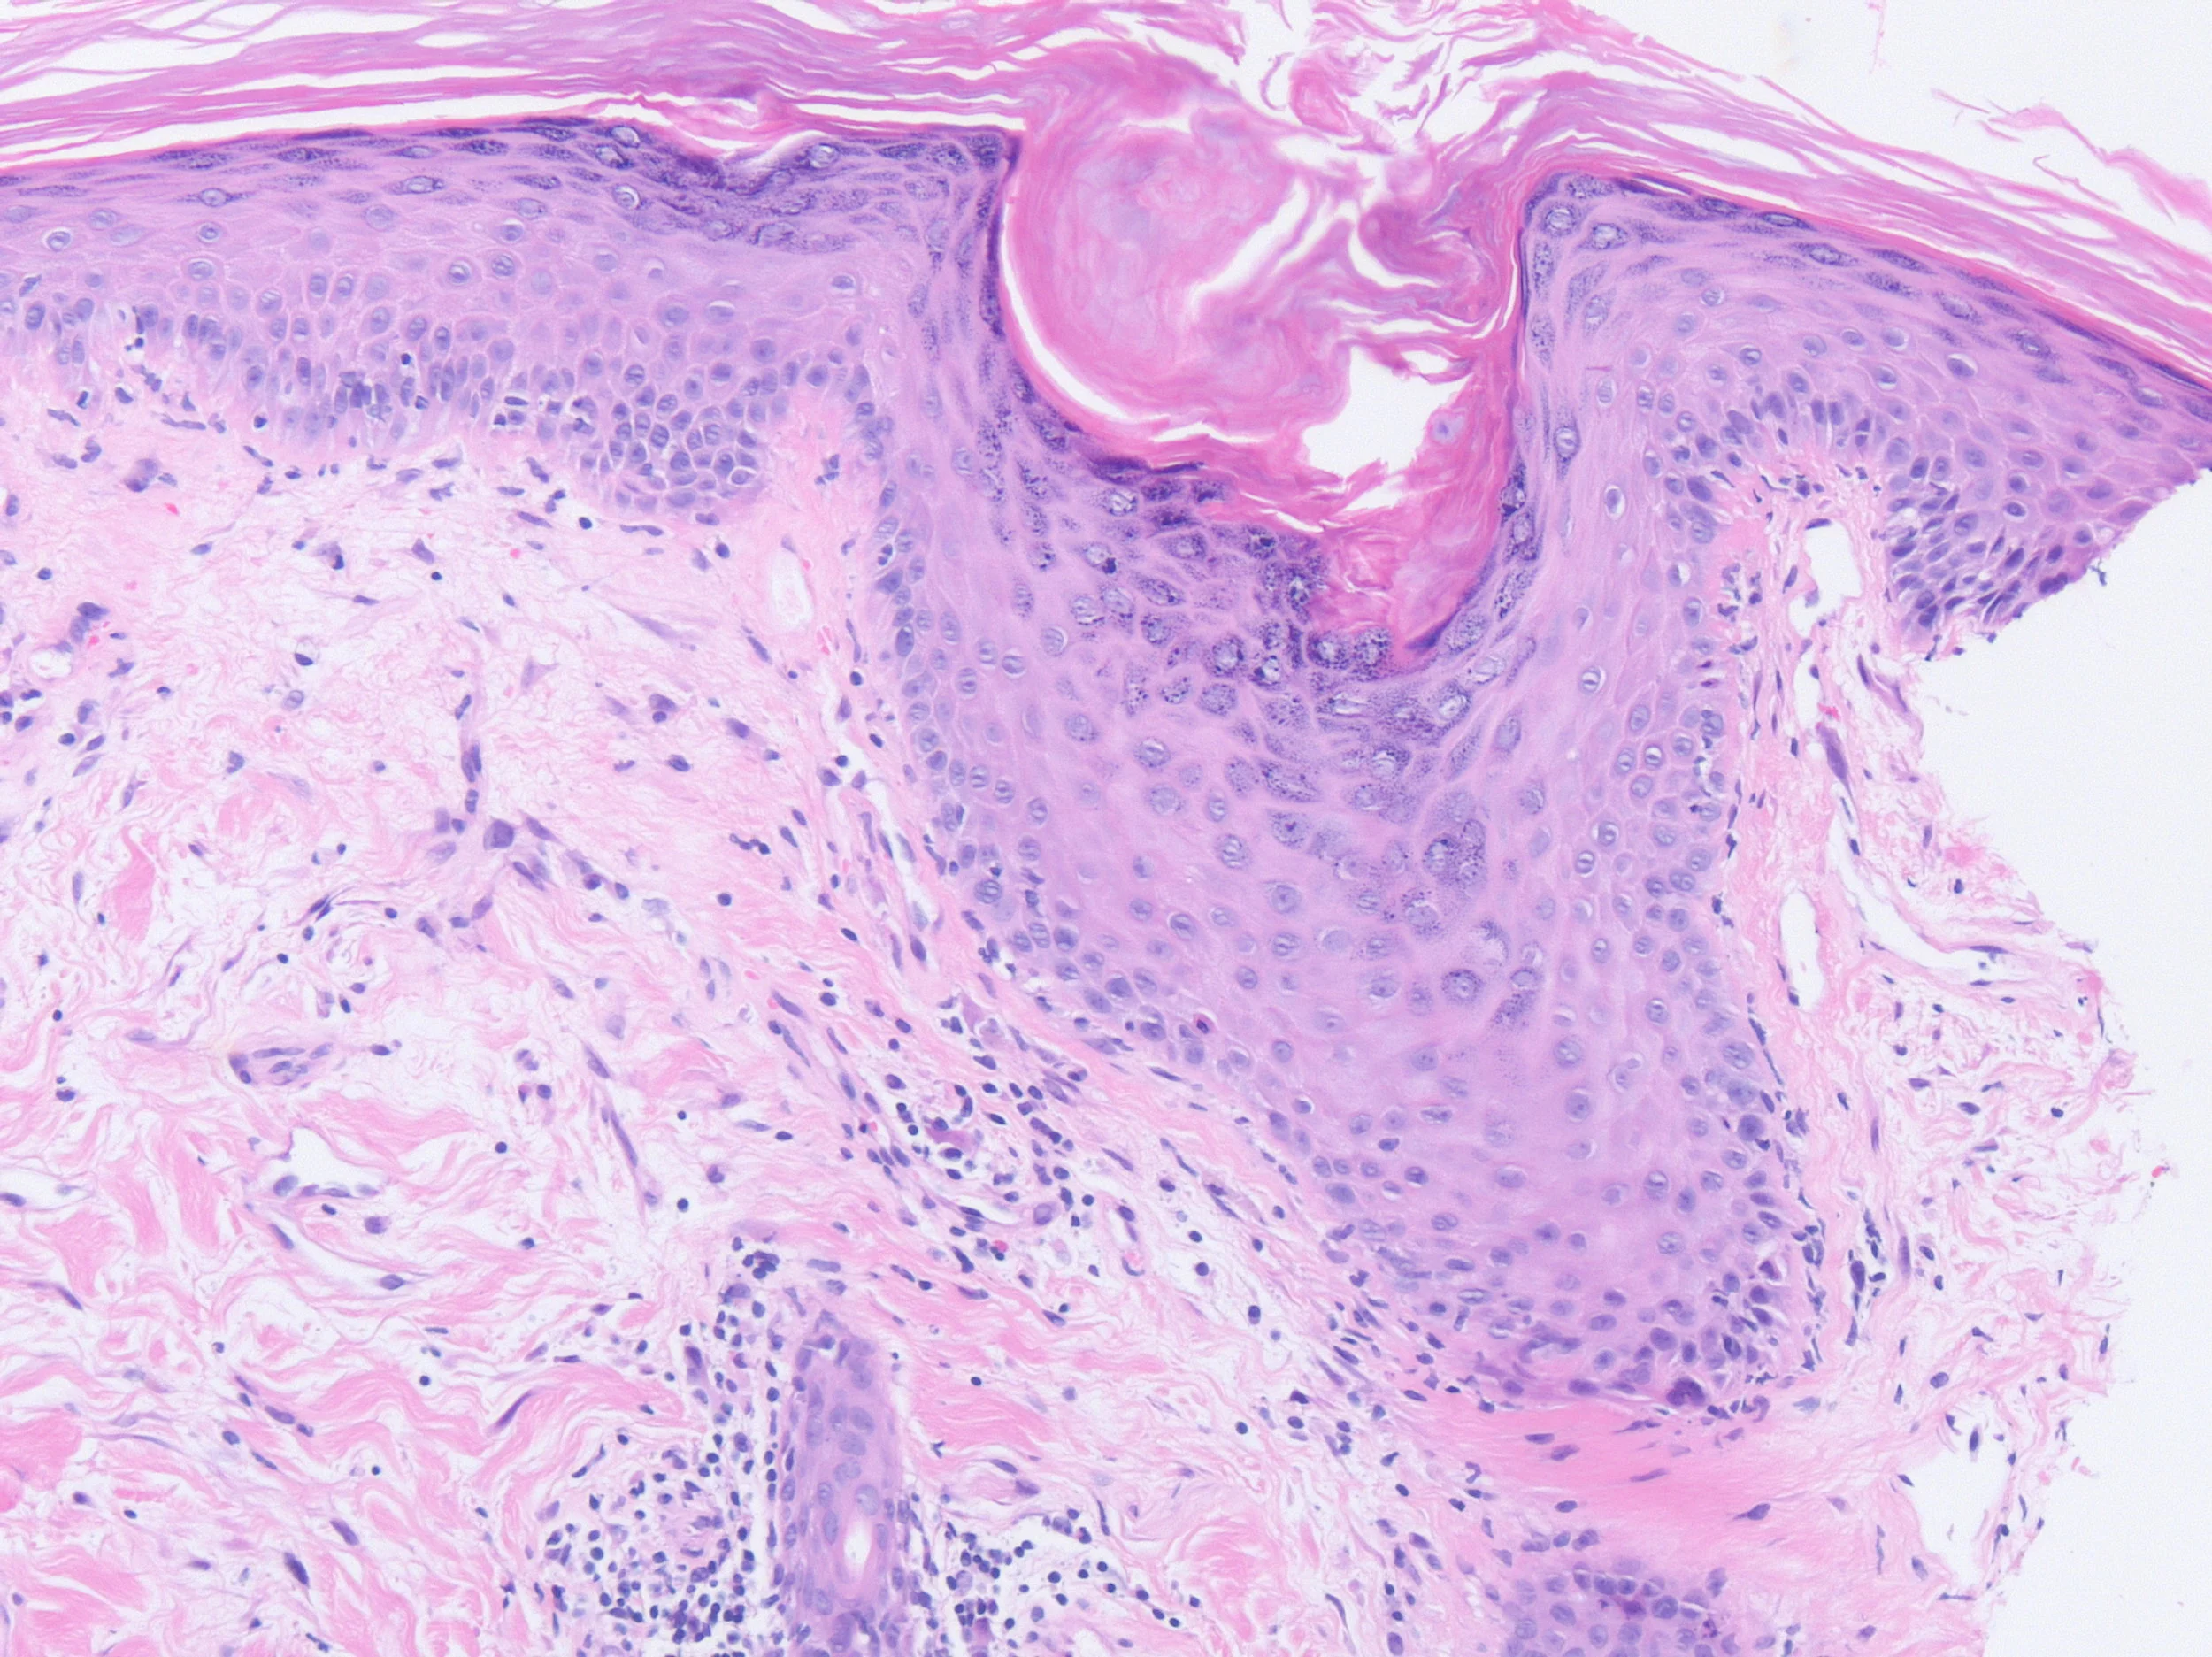

Left Shoulder Tip

Right Scalp